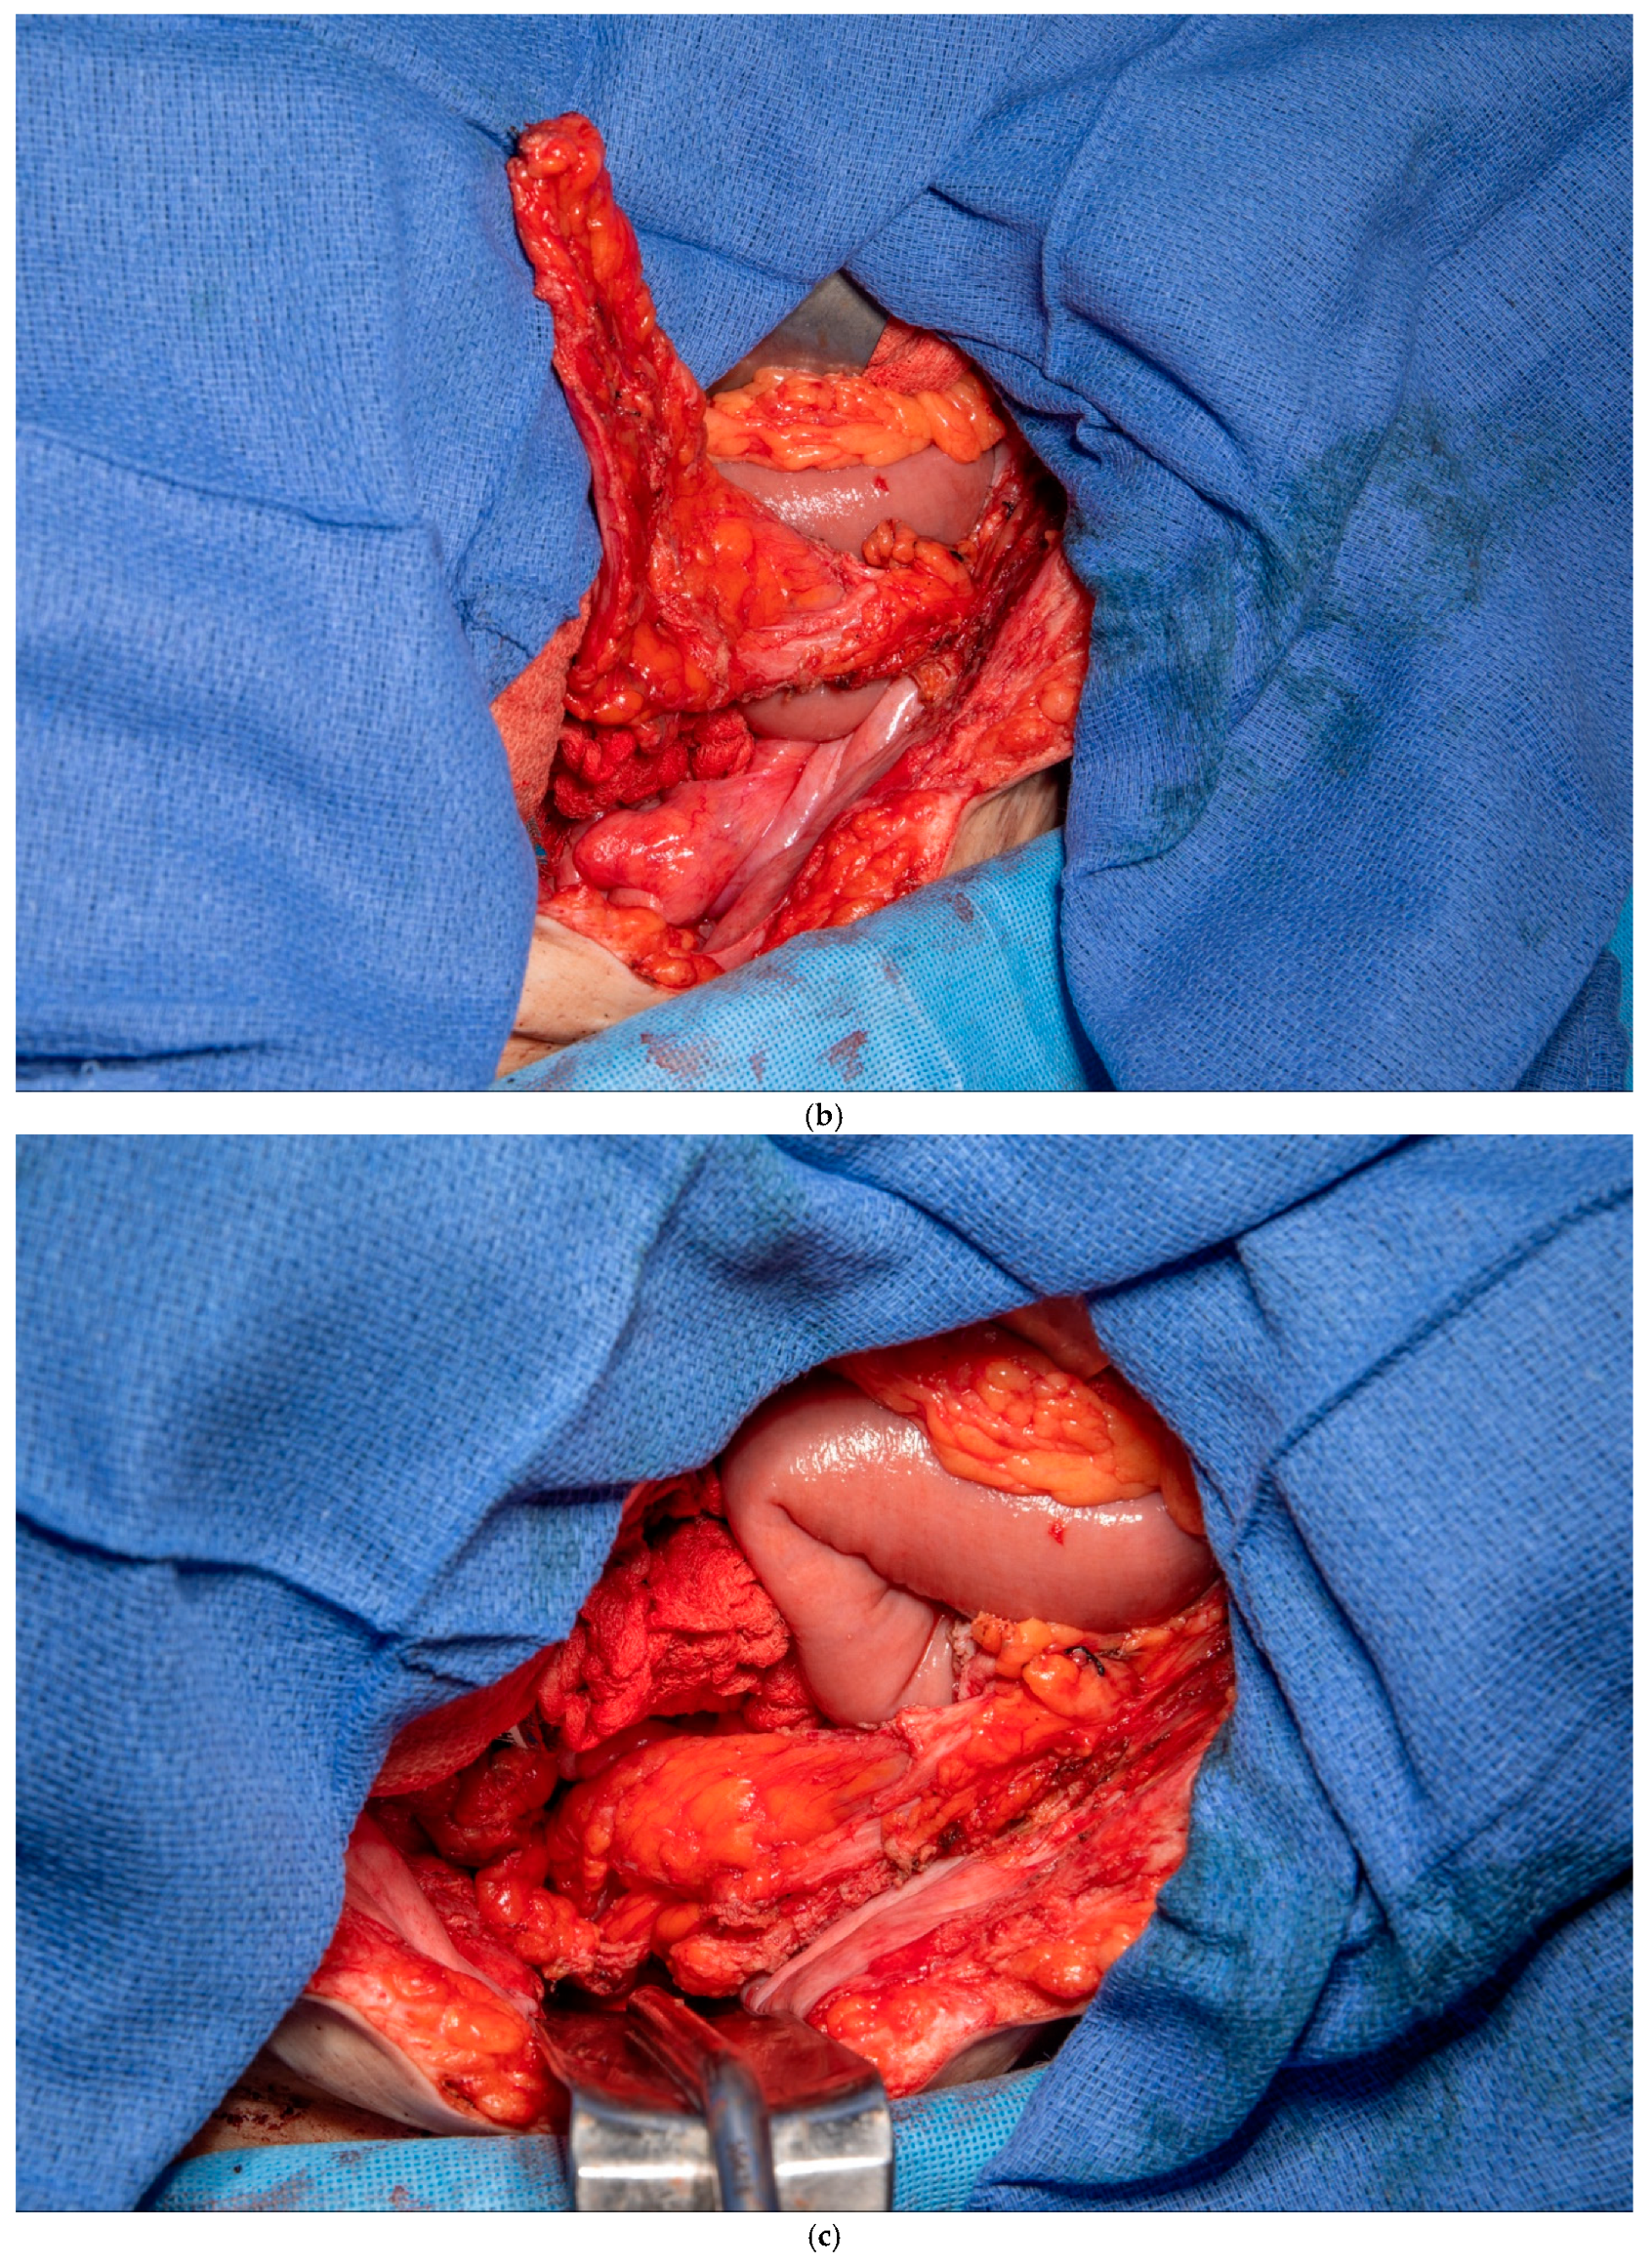

3.4. Gerota’s Fat Pad Flap

This patient was found to have no remaining greater omentum. She had a previous repair of a large ventral hernia with mesh, which rendered the rectus abdominus muscle no longer a viable option for a flap. She required a proctectomy because of multiple complex perianal fistulae despite diversion. While mobilizing the patient’s small intestine of the retroperitoneum, it was recognized that she had a very fatty Gerota’s fat pad overlying her right kidney. This Gerota’s fascia was opened, and the fat pad was peeled off the anterior wall of her kidney (See Figure 5a). With the assistance of a plastic surgeon, a posteromedial attachment of the flap was maintained to ensure adequate blood supply was preserved. Once fully mobilized, the flap easily reached and filled the pelvis (See Figure 5b,c). It was secured in place using 3-0 PDS sutures. A single drain was placed in the pelvis at the end of the case.

Figure 5.

(a) Pedicled Gerota’s fat pad flap elevated off the anterior surface of the right kidney. (Used with permission from the Mayo Foundation for Medical Education and Research; all rights reserved). (b) Empty pelvis after proctectomy. (Used with permission from the Mayo Foundation for Medical Education and Research; all rights reserved). (c) Pelvis filled and pelvic inlet occluded using the pedicled Gerota’s fat pad flap. (Used with permission from the Mayo Foundation for Medical Education and Research; all rights reserved).